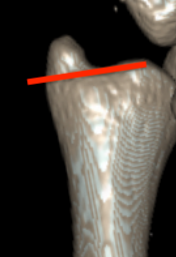

Classification ulna styloid fractures

| Type 1: Tip | Type 2: Base | Type 3: Proximal to styloid |